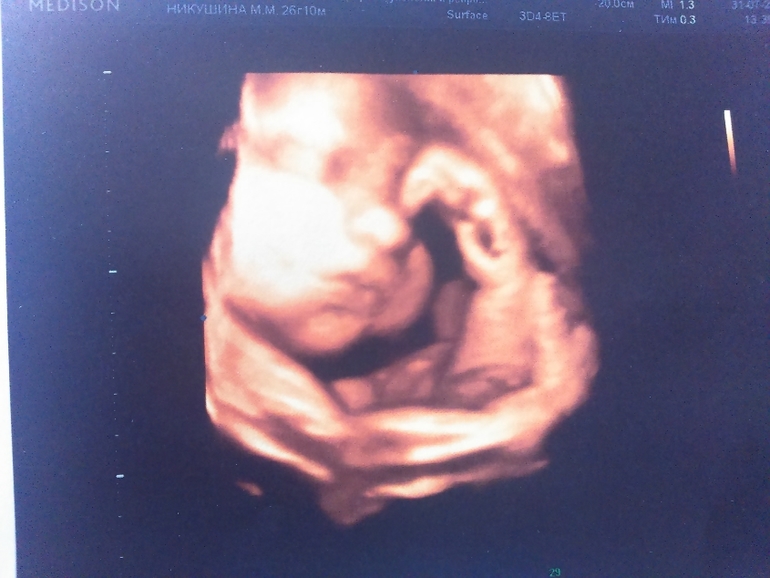

Лежит наш слоненок головой вниз, прижавшись к стенке матки носом, поэтому 3Д фотографии личика не очень вышли хорошо. зато причиндалы демонстрировал охотно)))

А сам сыночек такой классный)) хмурился, жмурился, плевался)) стопа уже 7 см

ну и пара фоточек (не очень лицо видно было, но разглядели папины щеки и губы и мой нос))))